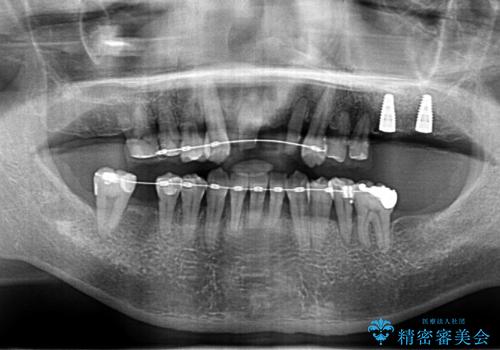

歯周病 、インプラント、 矯正 全顎治療

- 重度の歯周病に罹患しており、他院で「多数の歯を抜歯したのち、入れ歯を入れるしかない。」と言われ、入れ歯以外の方法がないか相談のため来院されました。

重度の歯周病で多数の歯を残せない問題、歯並び・噛み合わせの問題、欠損の問題、と多数の大きな問題が認められました。

このままの歯並びでは仮にインプラントを埋入したとしても歯ブラシがしづらく、また歯周病の問題が再発しやすい、と判断し矯正治療を行ったのちに歯周病治療、インプラント治療を行っていく治療計画としました。

インプラント治療に加え、歯周病に対しての再生治療や歯周ポケットの除去を行う歯周外科、矯正治療、と必要な治療は多岐に渡りましたが、最終的に安定した噛み合わせを得られたとともに、清掃のしやすい口腔内環境を確立できました。